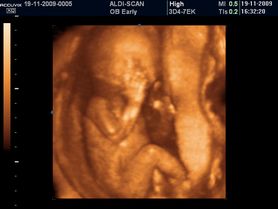

Płód w 11 tygodniu ciąży (zdjęcia 3D)